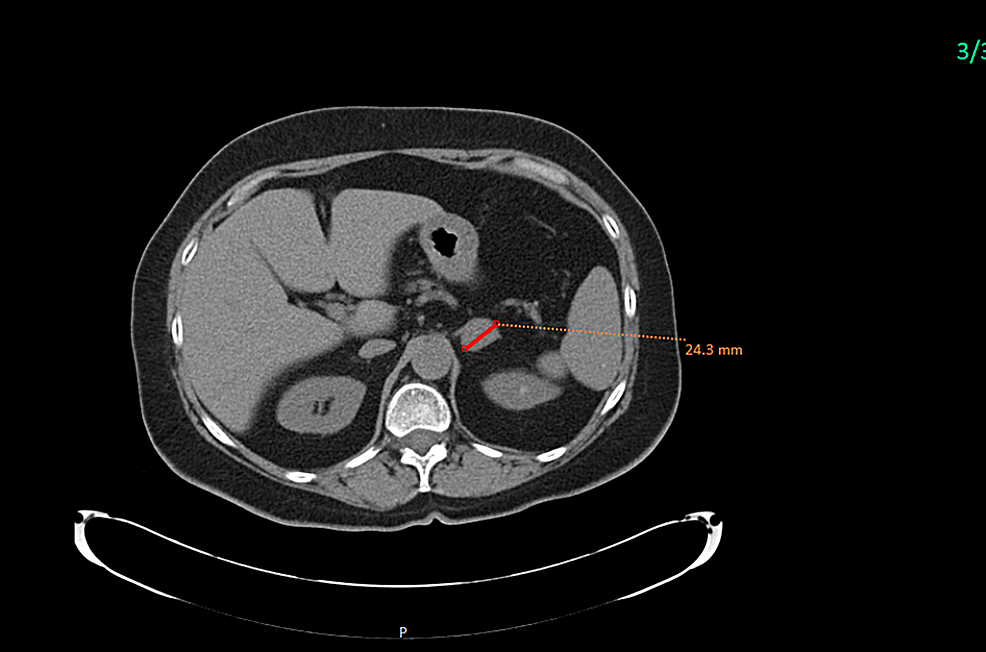

Cystic Neuroendocrine Tumor in Tail of the Pancreas Pancreas Case Endocrine Ct Scan ct scans are often the initial imaging study for a patient presenting with signs or. Your doctor may recommend testing your blood or your urine for signs. neuroendocrine tumors are cancers that can develop anywhere endocrine cells are present. As a separate examination, it is usually. the book “imaging in endocrine disorders” is aimed at endocrinologists, radiologists. Endocrine Ct Scan.